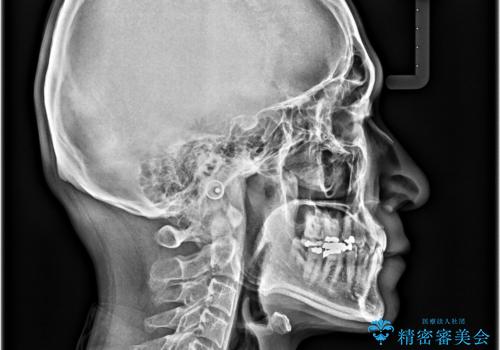

ディープバイトが改善され、睡眠時の食いしばりも緩和され、顎への負担が軽減されました。